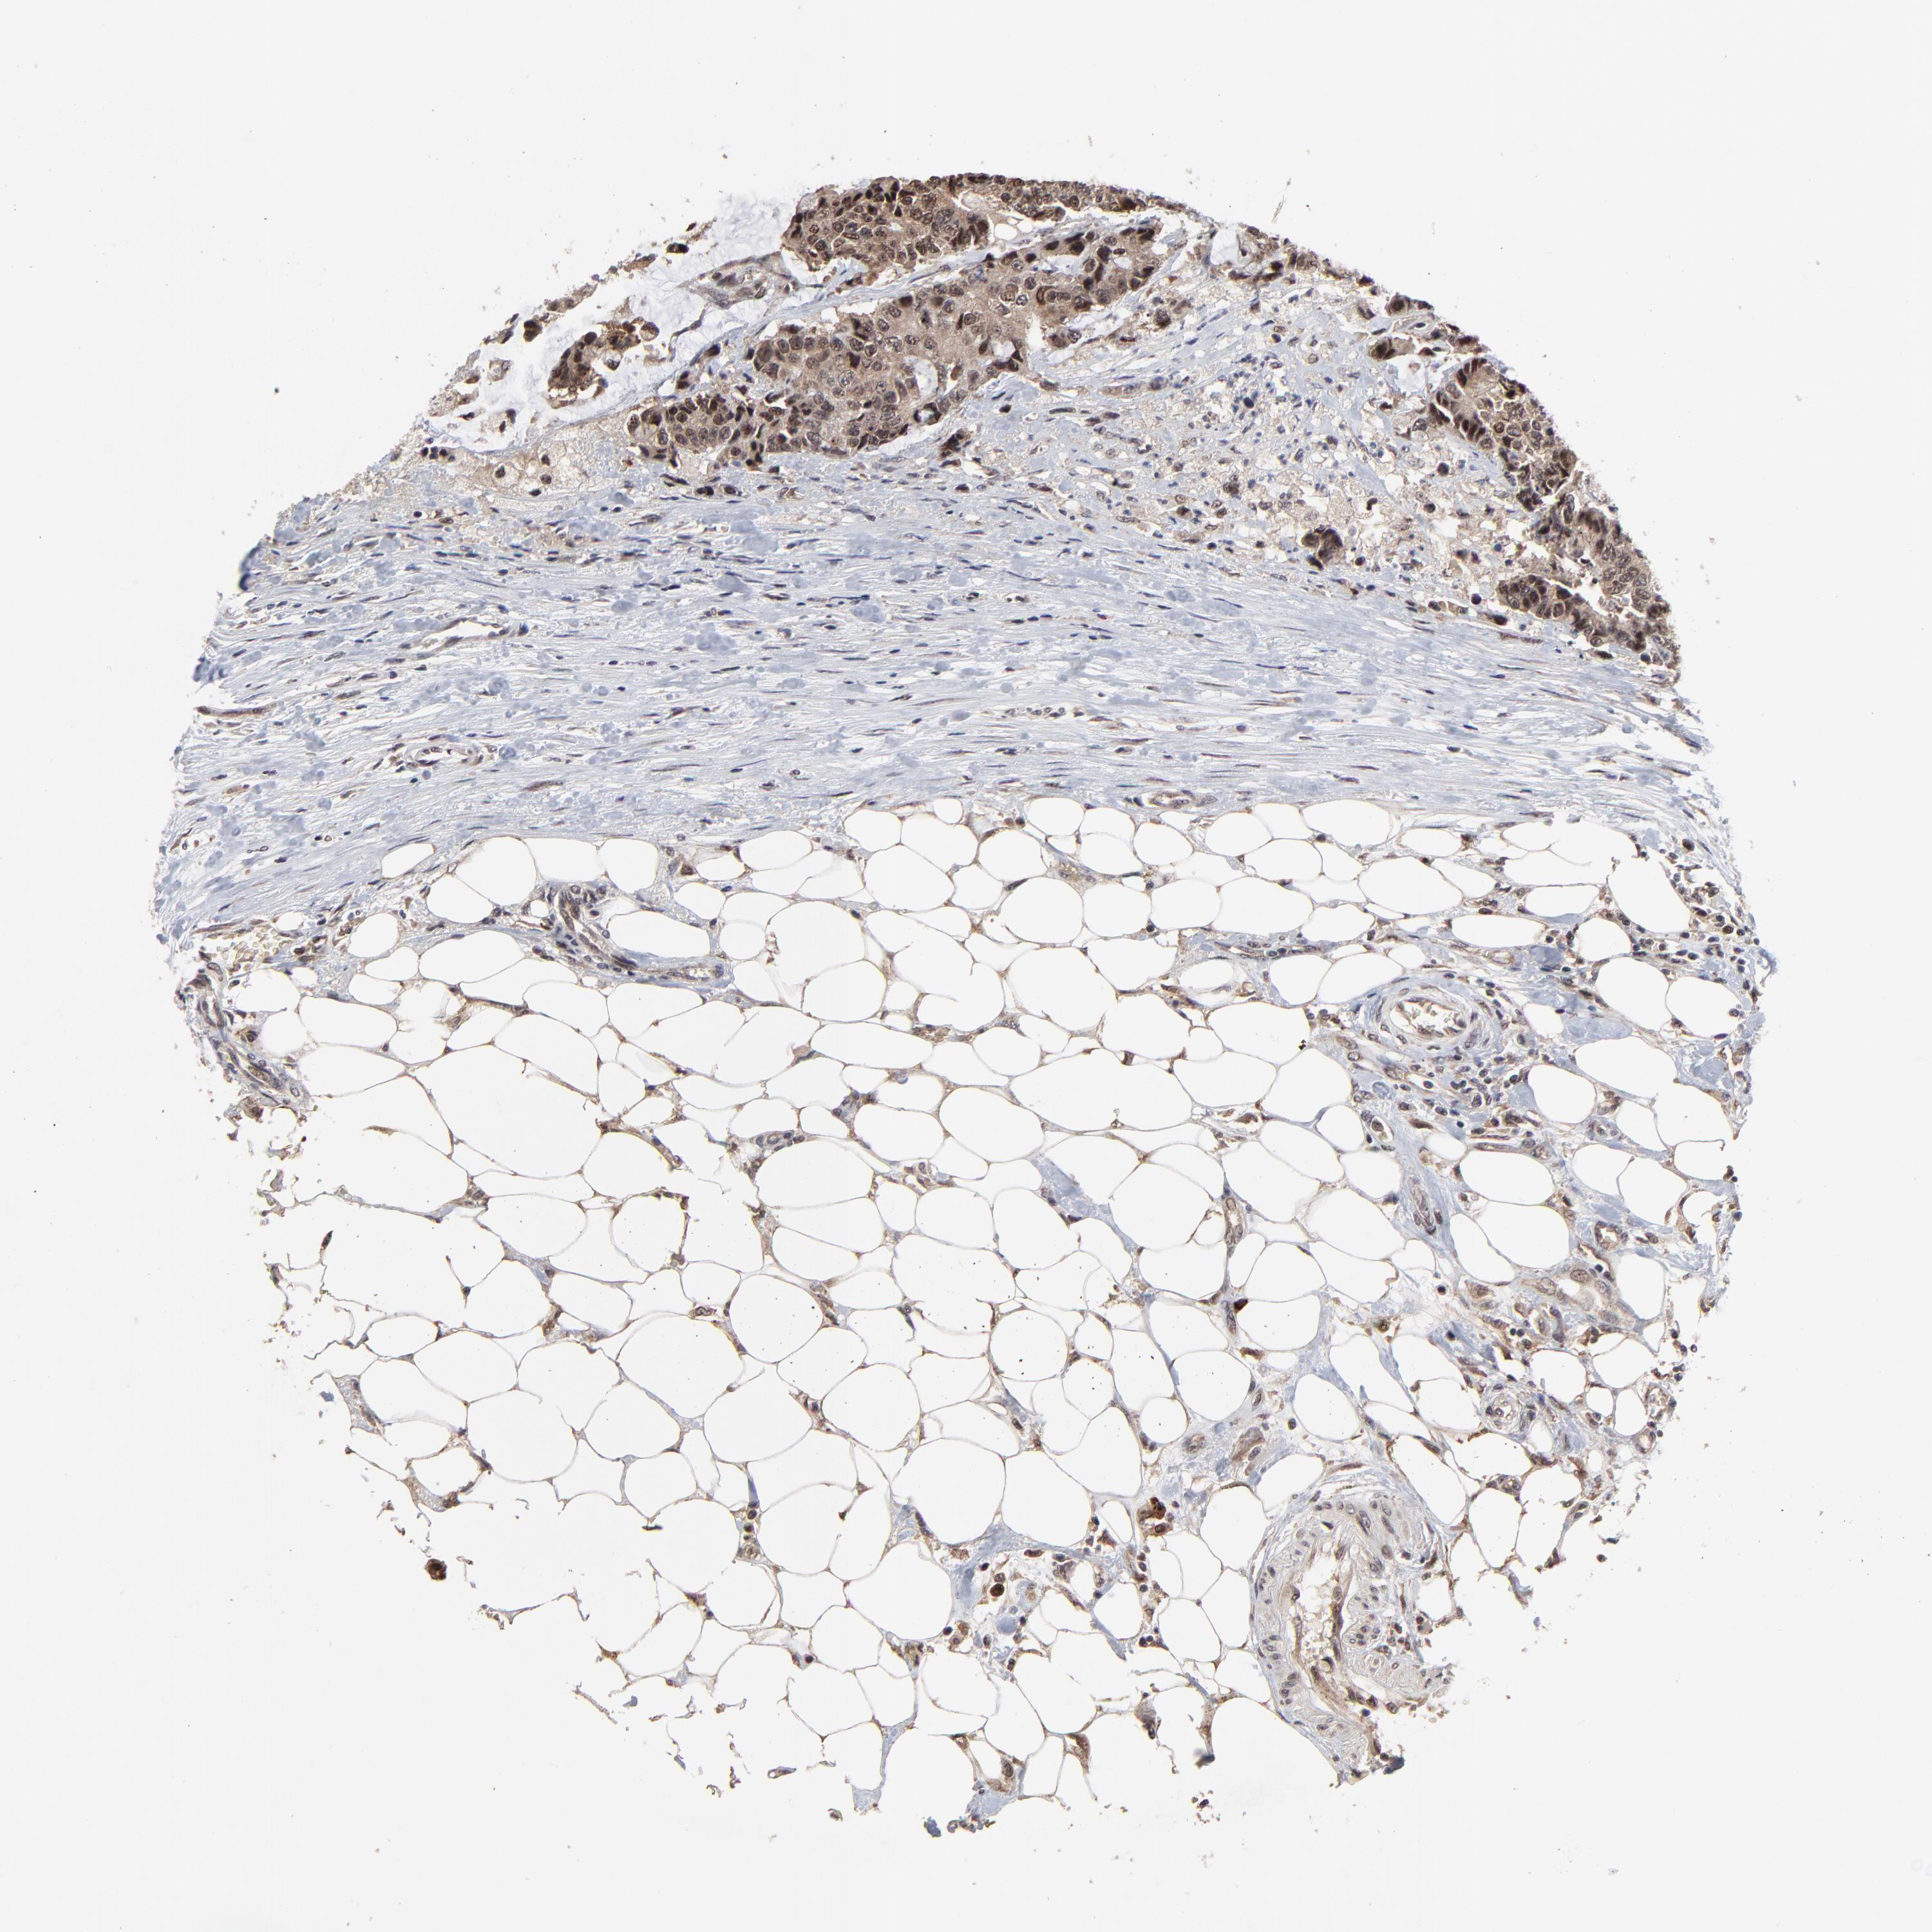

CANCER COLORECTAL CANCER Show tissue menu

Colorectal cancer

Colon adenocarcinoma